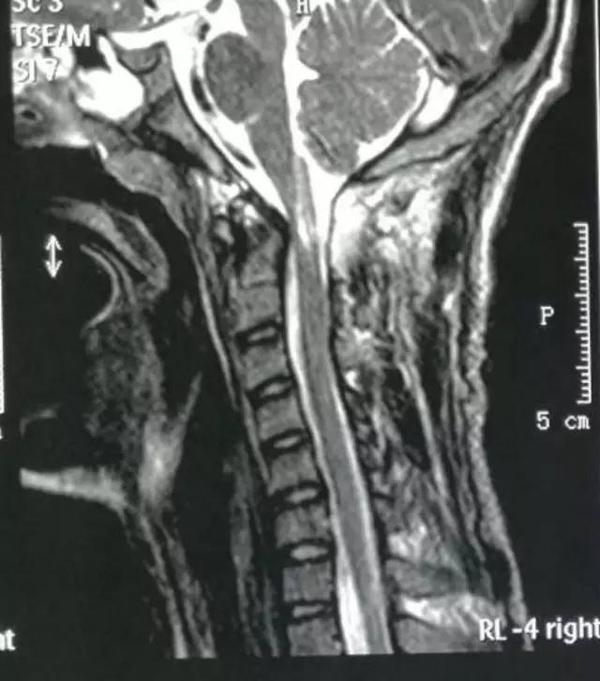

术前影像资料

1、脊髓损伤

2、颅颈畸形:寰枢椎半脱位,齿状突不连续